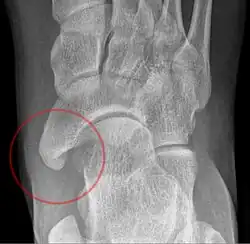

Type 2

Cornuate navicular bone